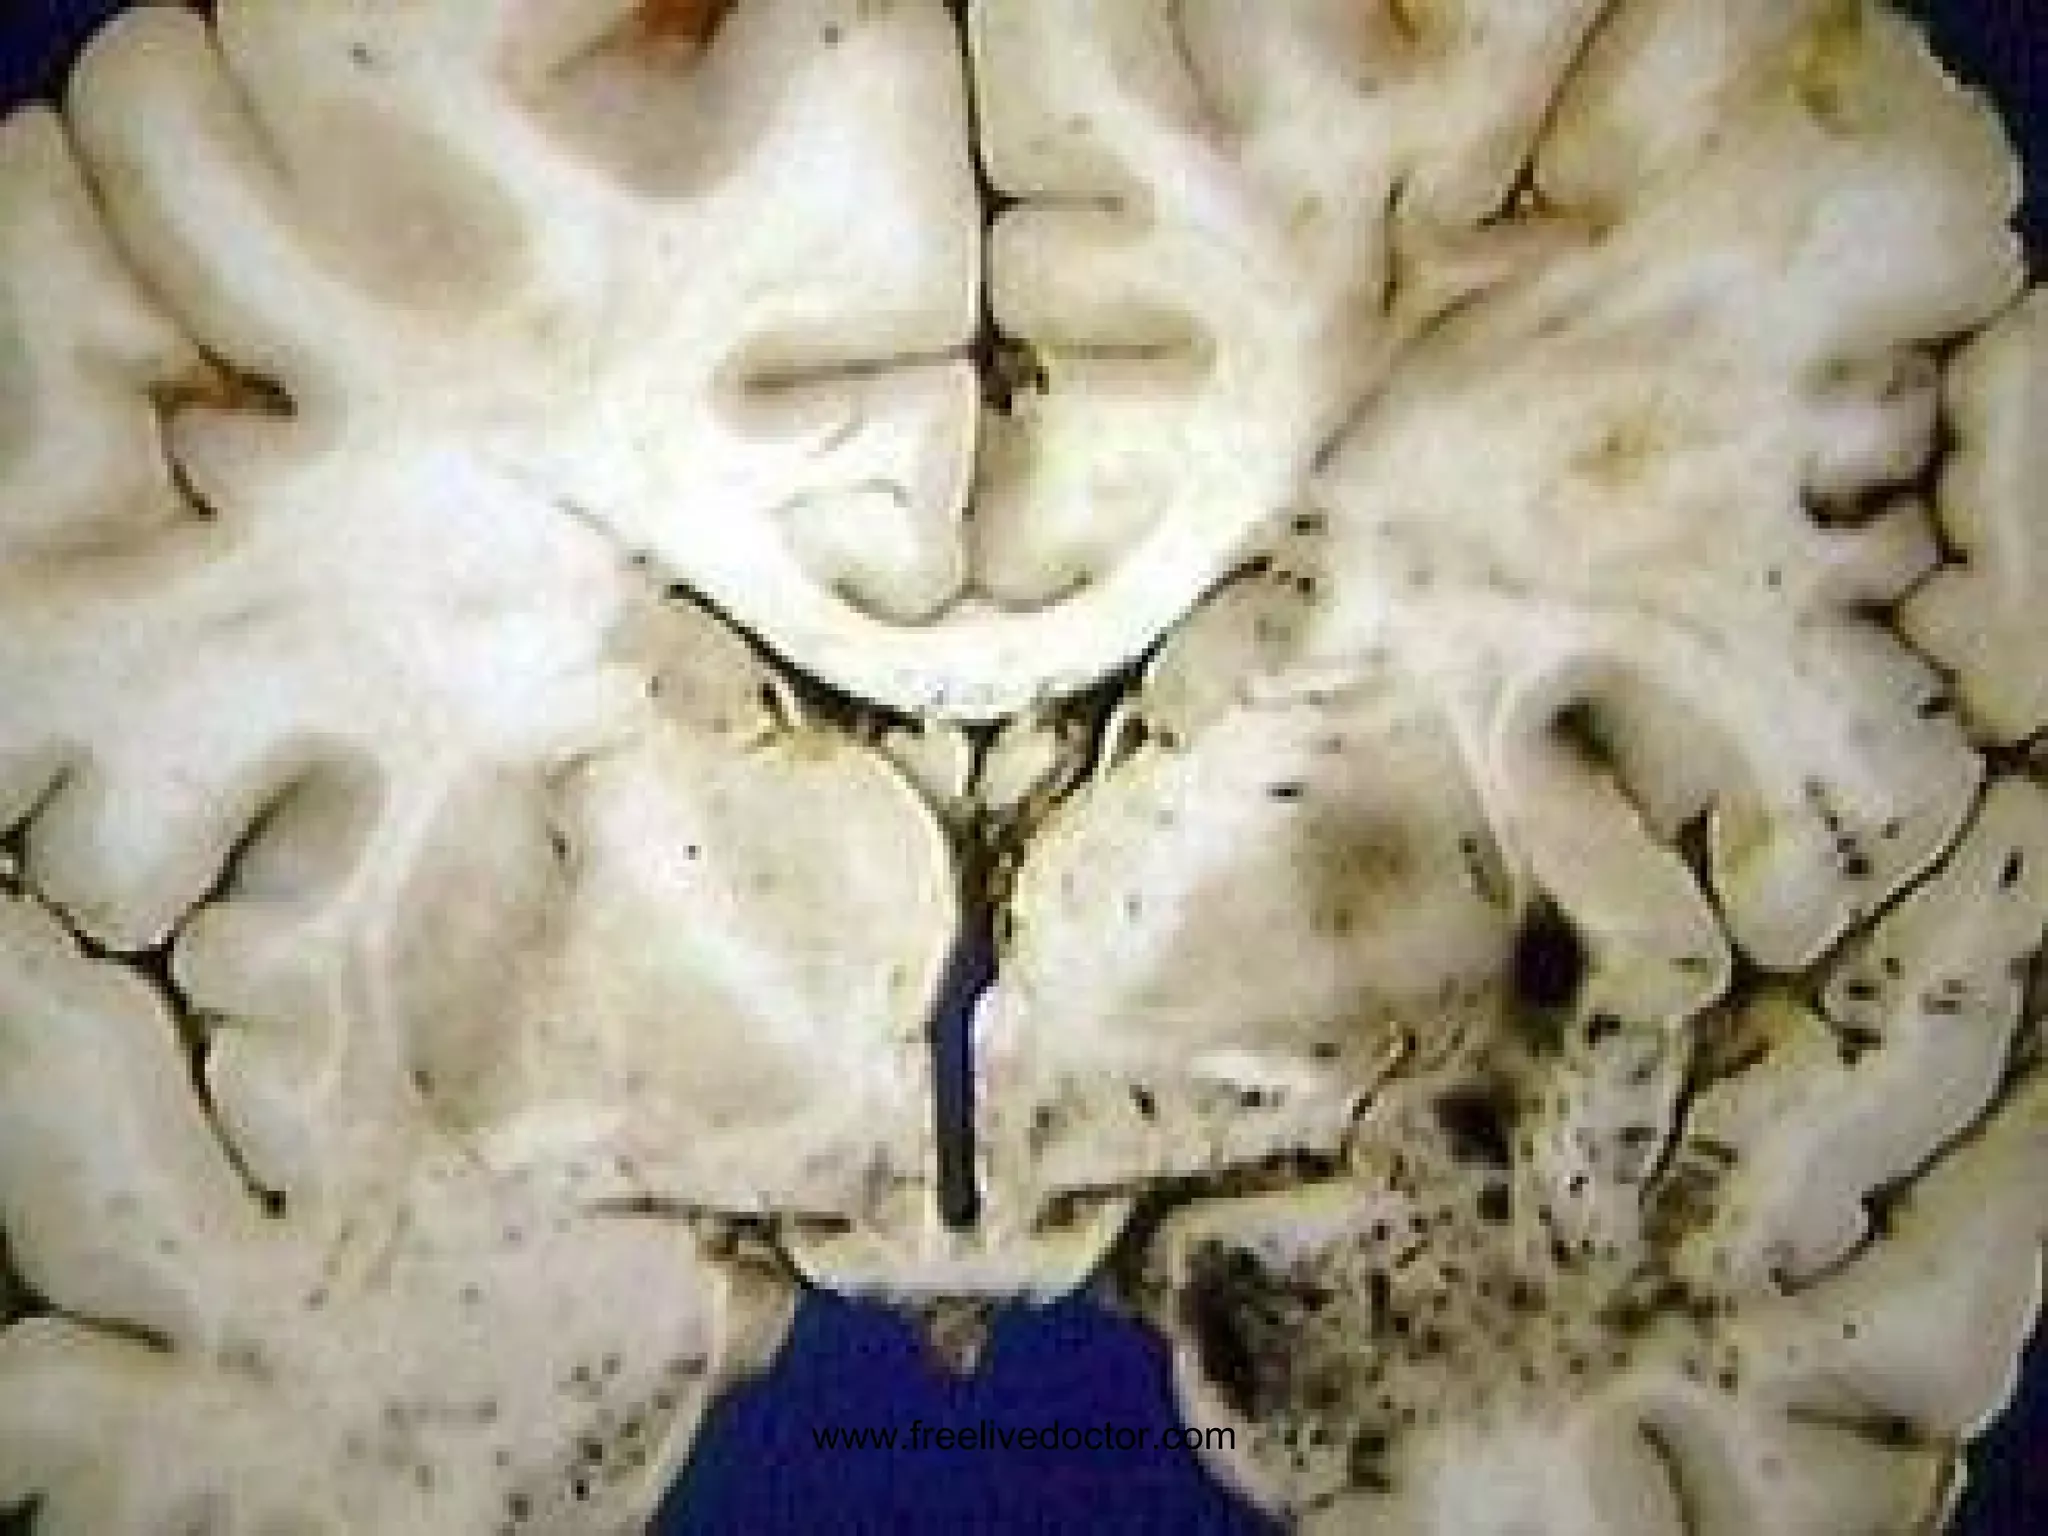

LACUNAR INFARCTS www.freelivedoctor.com

“ SLIT” HEMORRHAGE(s) www.freelivedoctor.com

HYPERTENSIVE CVA Intracerebral Basal Ganglia Region (lenticulostriate arteries of internal capsule,  putamen) www.freelivedoctor.com

HYPERTENSIVE CVA www.freelivedoctor.com